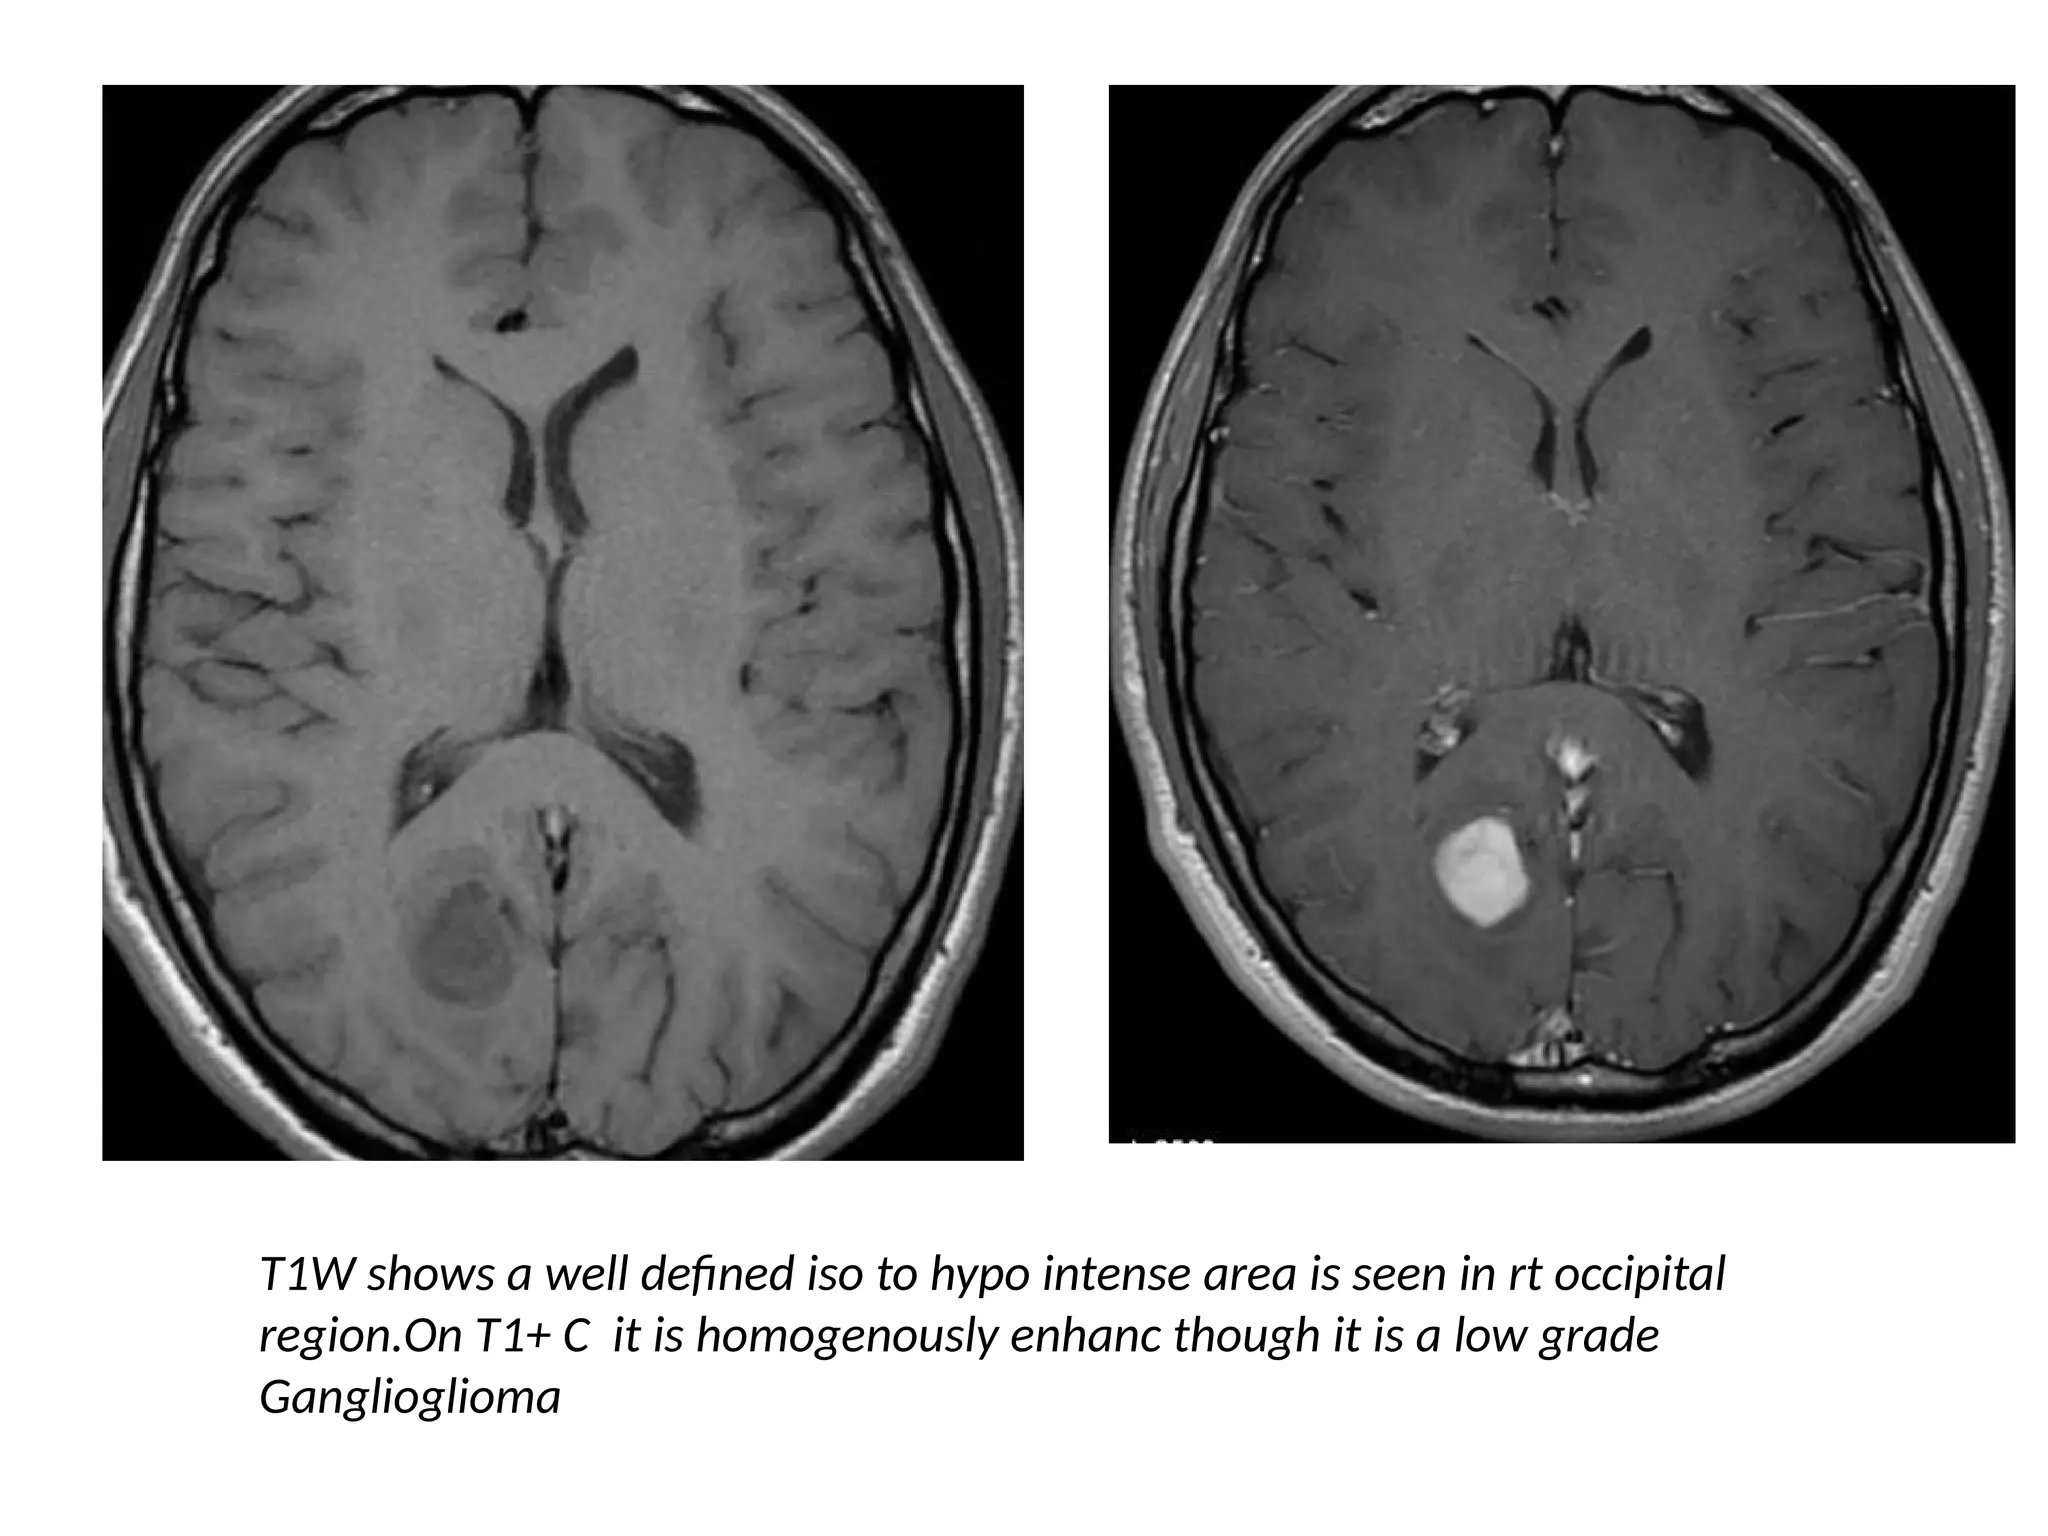

T1W shows a well defined iso to hypo intense area is seen in rt occipital

region.On T1+ C it is homogenously enhanc though it is a low grade

Ganglioglioma

• Gangliogliomas and pilocytic astrocytomas are the exceptions to

this rule: they are low-grade tumors, but they enhance vividly.